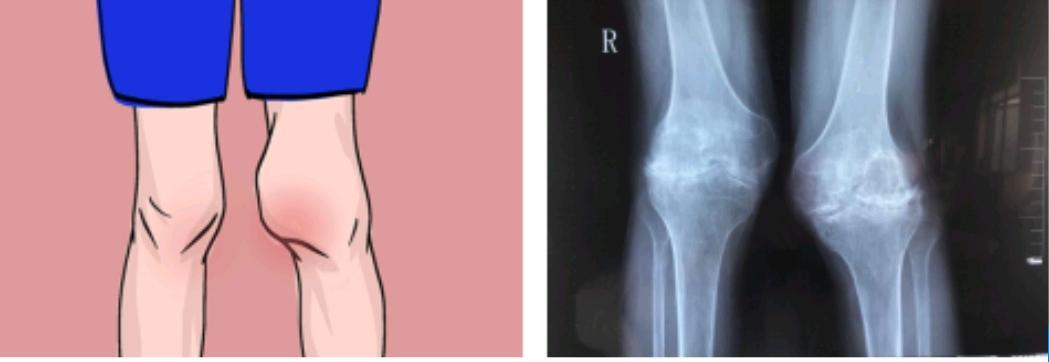

据权威数据统计,血友病患者关节出血最常受累的关节依次为:膝关节、踝关节、肘关节、髋关节、肩关节和腕关节。由于关节反复出血,关节腔内的血液会刺激滑膜引发滑膜炎,而炎症刺激增厚的滑膜会因为活动时的挤压、撕裂而加重出血,从而形成了恶性循环,最终导致患者出现持续性关节肿胀和活动障碍。与此同时,关节内反复出血会导致血友病性关节炎,出现关节软骨的破坏,关节间隙变窄,软骨下骨质缺损,骨质疏松,肌肉废用性萎缩,最终导致患者关节畸形,关节活动严重受限,给生活带来严重的不便与痛苦。

“53岁的罗先生,3岁时诊断为血友病,但由于经济的原因一直未能系统治疗,长年累月的关节内出血导致患者双膝关节严重破坏变形,行走功能严重受限,给患者的生活带来了相当的困难,在我们关节中心综合评估后为他行了左侧全膝关节置换术,手术安全顺利,术后康复良好,关节功能明显改善,面对着术后膝关节功能的革命性改善,罗先生很高兴。”陈群群讲述了一个血友病患者的故事。